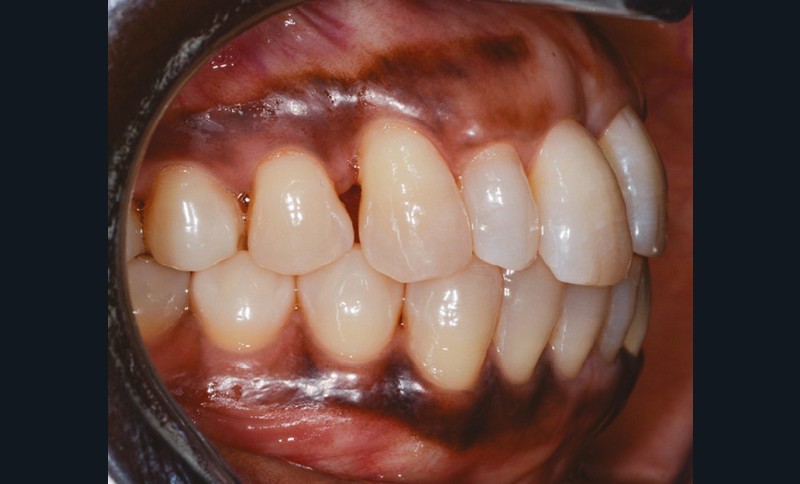

L’observation clinique après traitement parodontal initial révèle, au niveau interarcade, des rapports de classe I molaire bilatéraux associés à des rapports de bout à bout incisif. Dans la dimension verticale, elle présente une légère infraclusion antérieure. On ne note pas d’anomalie de la dimension transversale (fig. 3 à 5). À l’examen intra-arcade, on constate des diastèmes maxillaires interincisifs (1 mm), en distal de 13 (0,5 mm) et de 24 (1 mm) ainsi que des malpositions unitaires (linguoversion de 12, rotation mésio-vestibulaire disto-linguale de 24). À la mandibule, on observe une couronne céramométallique au niveau de 32 plus large de 1,5 mm que les autres incisives ainsi qu’une rotation mésio- linguale de 35 (fig. 6 à 8). En diduction, on note une interférence au niveau de 24.